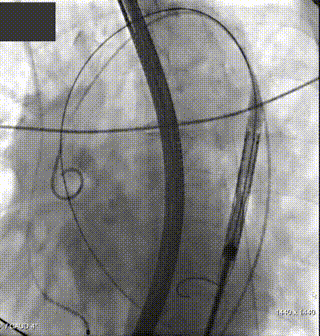

1.经右侧颈静脉留置临时起搏电极;以左侧股动脉为辅入路,并在超声指导下穿刺右侧股动脉为主入路;

2.主动脉根部造影,示双侧冠脉灌注良好;

3.直头导丝跨瓣,交换超硬导丝支撑;

4.180次/分快速起搏下以TaurusAtlas 22mm 球囊进行预扩张,扩张同时造影示轻微腰征,无造影剂渗漏,被推开的左冠瓣瓣叶未累及左冠开口,左冠显影明显;

5. 根据术前评估及球囊预扩情况,选择沛嘉TaurusElite AV26号瓣膜进行植入,在120次/分快速起搏下释放瓣膜,第一次释放至工作位发生下滑;

6. 回收后进行重新定位释放,释放完毕后超声评估示平均跨瓣压差15mmHg,超声、造影评估示中量瓣周漏、少量瓣中漏,瓣膜整体下滑明显,遂行瓣中瓣策略;

7. 选择沛嘉TaurusElite AV26号瓣膜执行瓣中瓣策略,第二个瓣膜释放后造影示瓣周漏改善不明显,遂选用TaurusAtlas 22mm 球囊行后扩张;

8. 扩张后跨瓣压差降至8mmHg,造影示轻微瓣周漏,患者血流动力学指标改善明显,手术圆满成功。